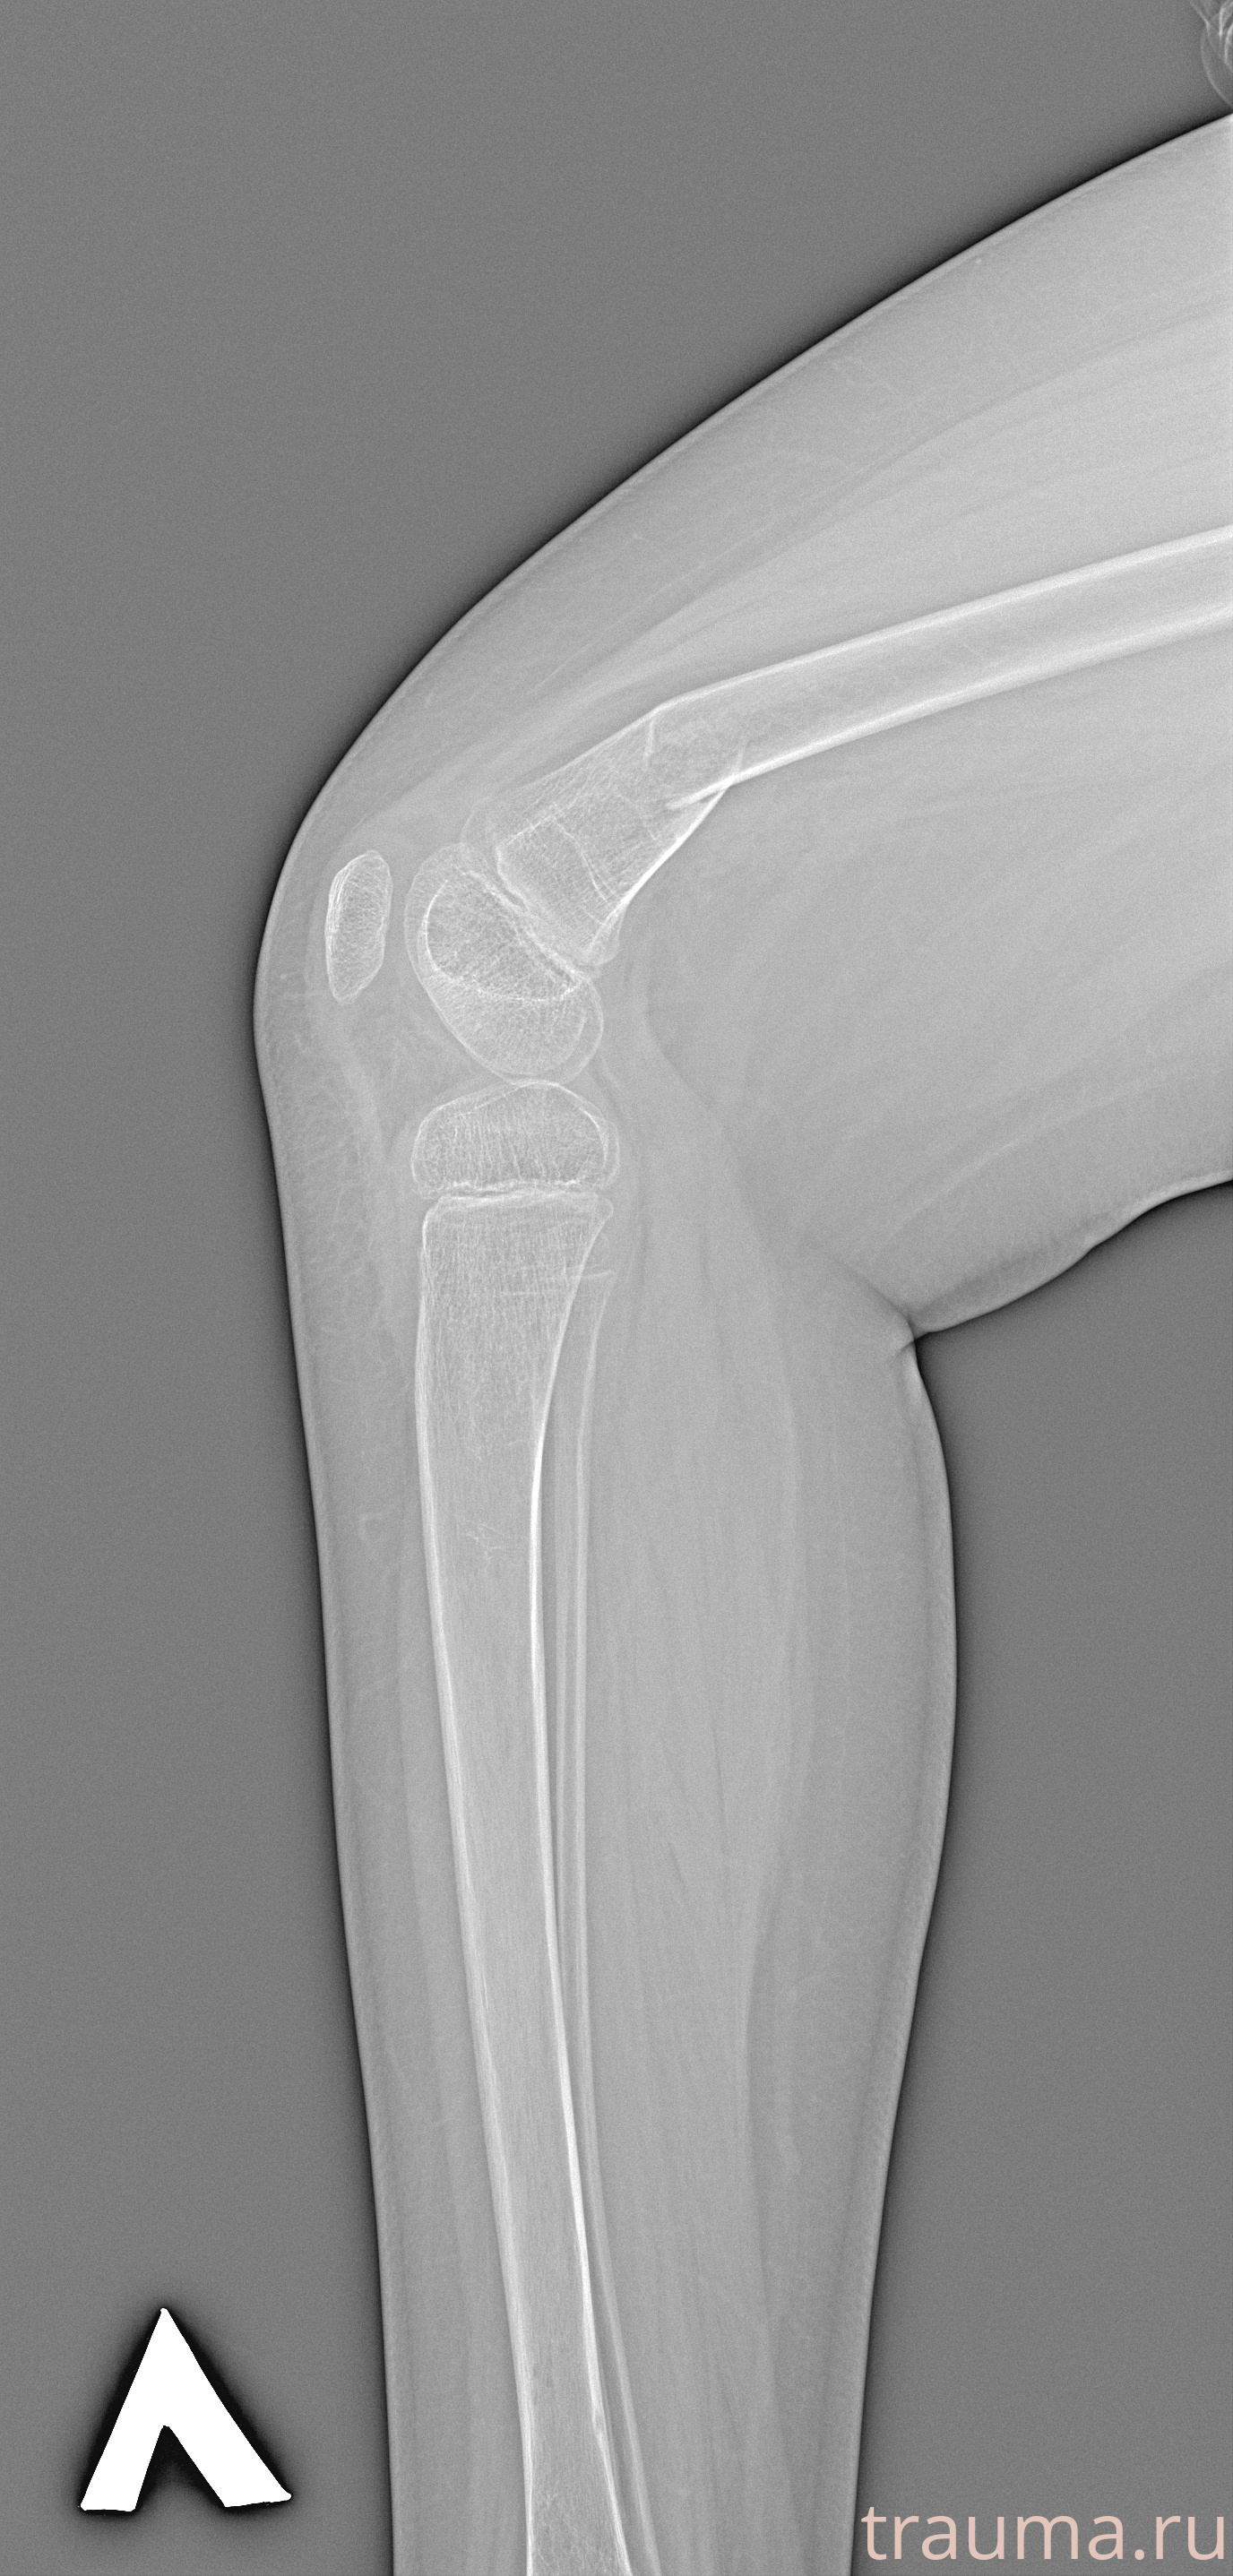

Рентгенограммы